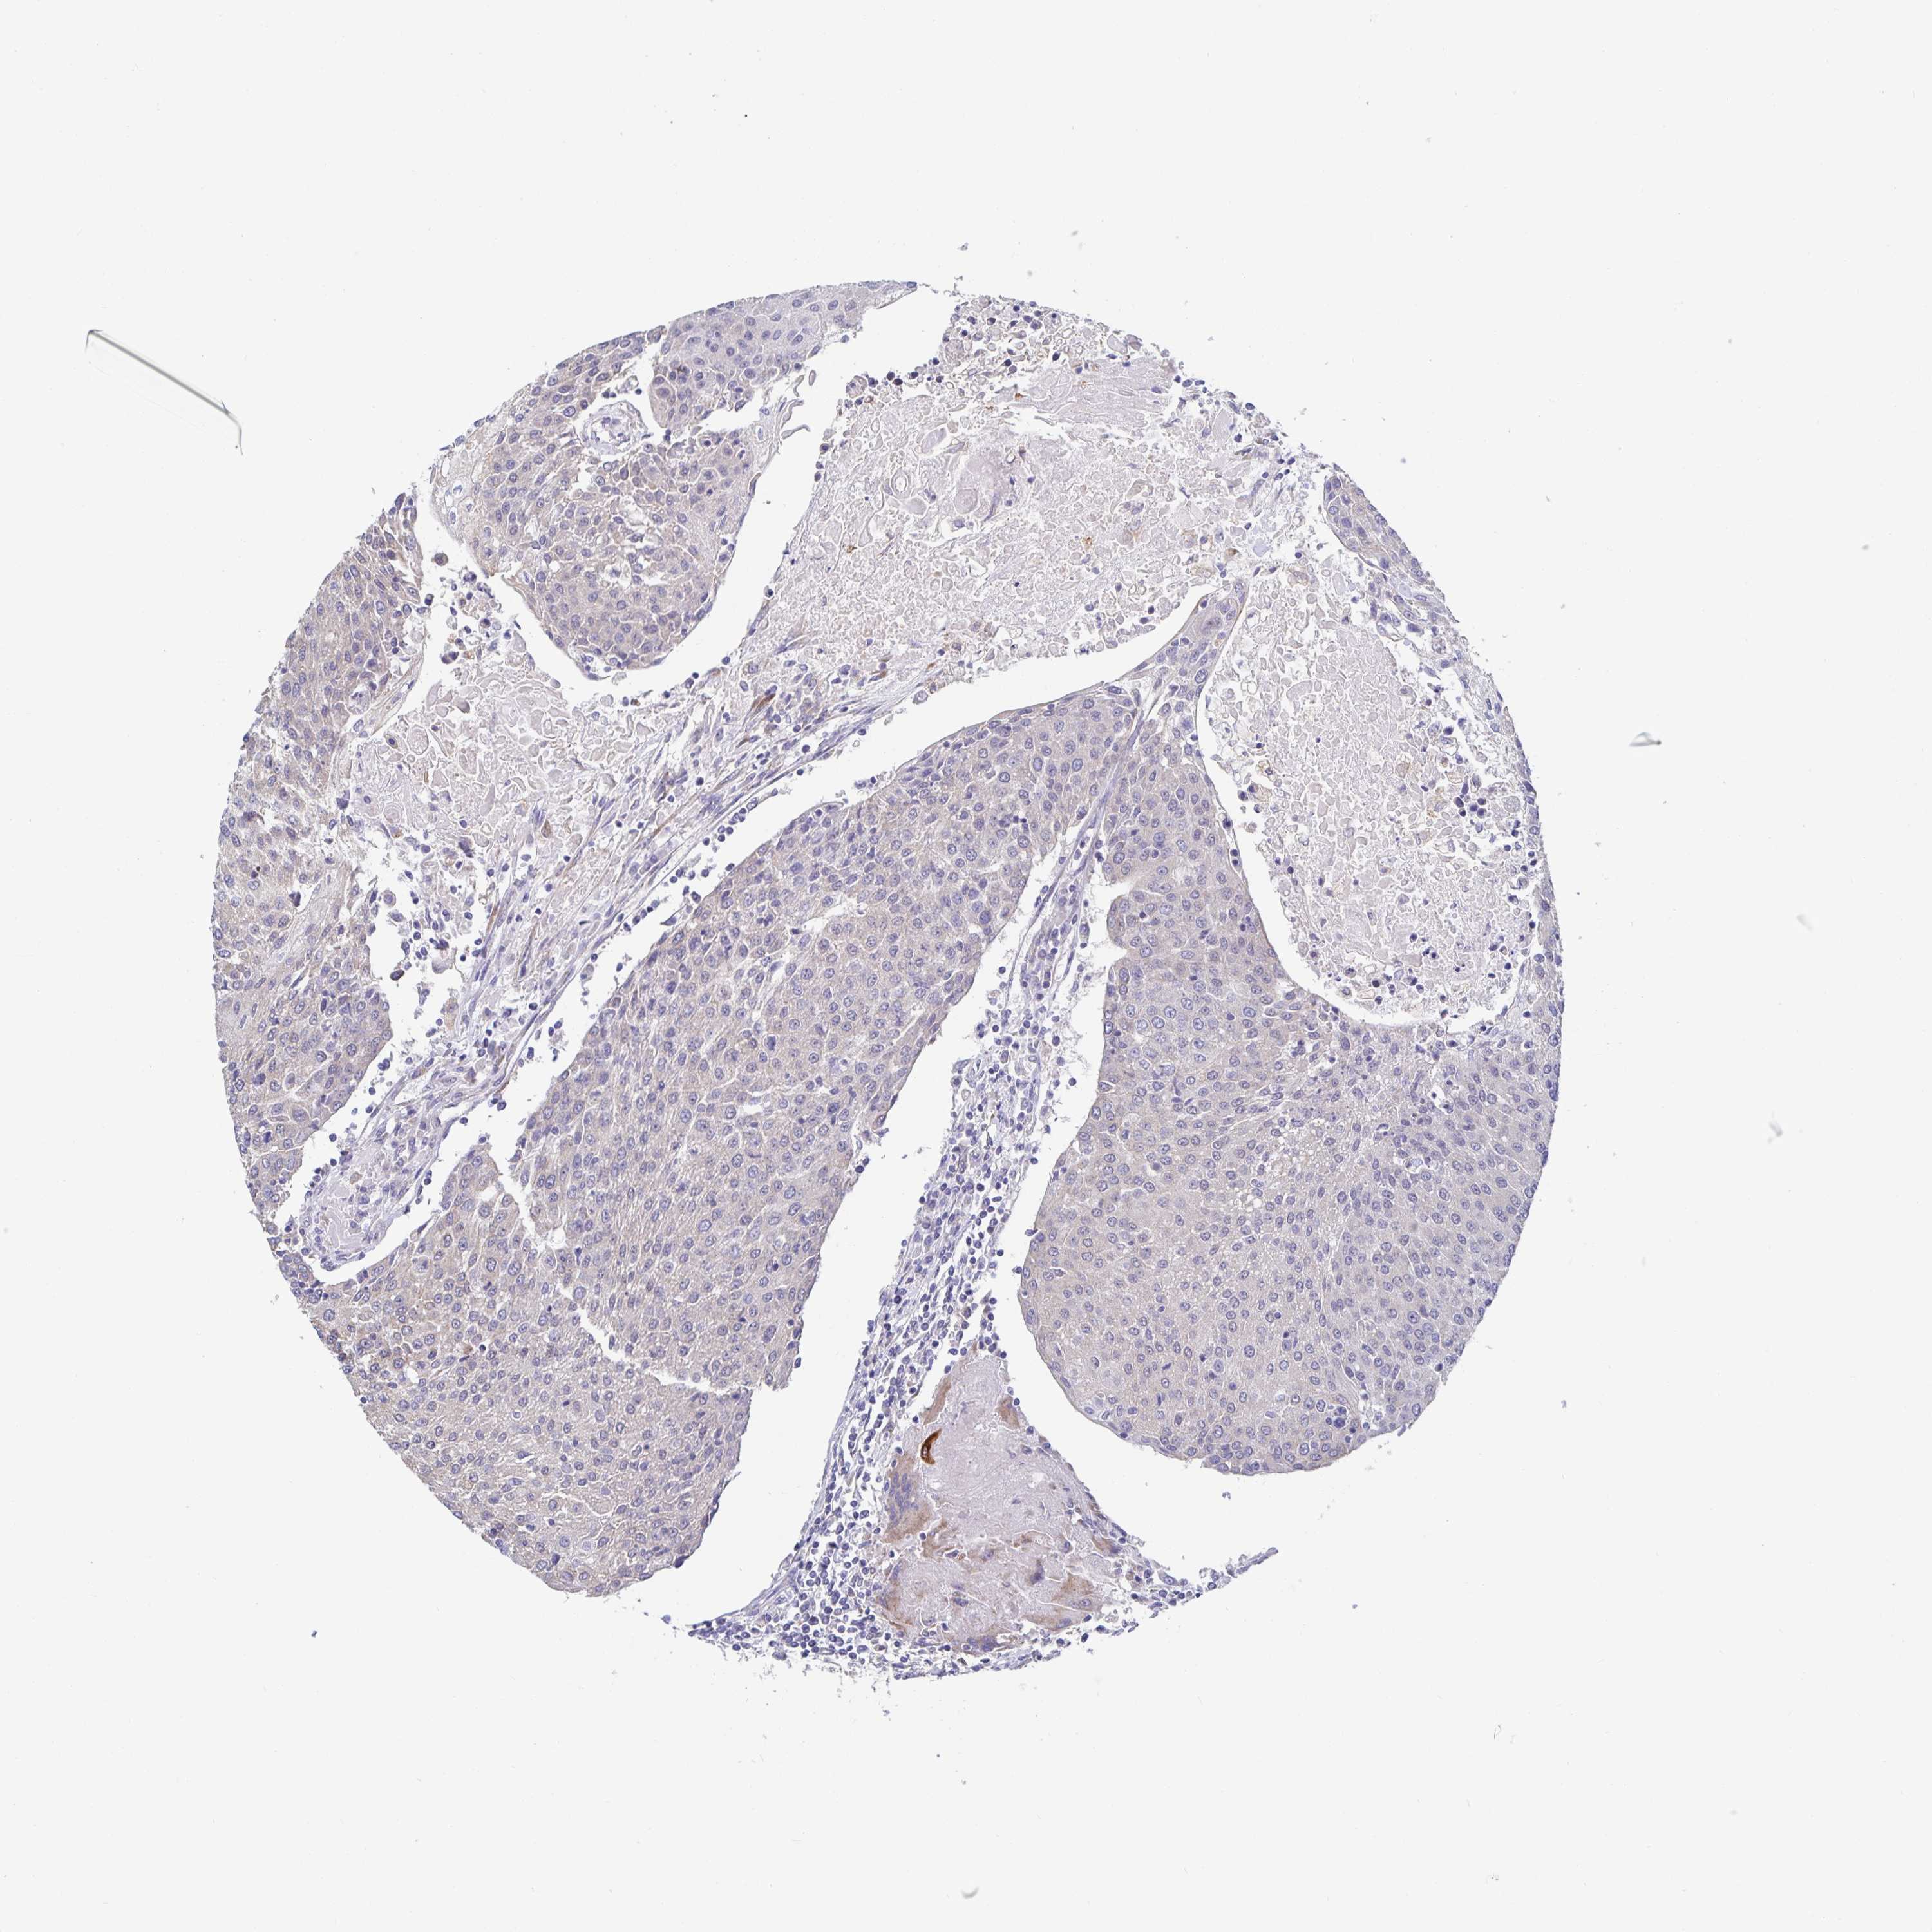

UROTHELIAL CANCER - Protein expressioni

A mouse-over function shows sample information and annotation data. Click on an image to view it in a full screen mode. Samples can be filtered based on level of antibody staining by selecting one or several of the following categories: high, medium, low and not detected. The assay and annotation is described here.

Note that samples used for immunohistochemistry by the Human Protein Atlas do not correspond to samples in the TCGA dataset.

Antibody stainingi

Antibody staining in the annotated cell types in the current human tissue is reported as not detected, low, medium, or high, based on conventional immunohistochemistry profiling in selected tissues. This score is based on the combination of the staining intensity and fraction of stained cells.

Each image is clickable and will lead to virtual microscopy that enables deeper exploration of all samples and also displays staining intensity scores, fraction scores and subcellular localization as well as patient and tissue information for each sample.

Antibody HPA059975

Staining

High

Medium

Low

Not detected

Intensity

Strong

Moderate

Weak

Negative

Quantity

>75%

75%-25%

<25%

None

Location

Nuclear

Cytoplasmic/membranous

Cytoplasmic/membranous,nuclear

Urothelial carcinoma, High grade

Urothelial carcinoma, NOS

Urothelial carcinoma, Low grade